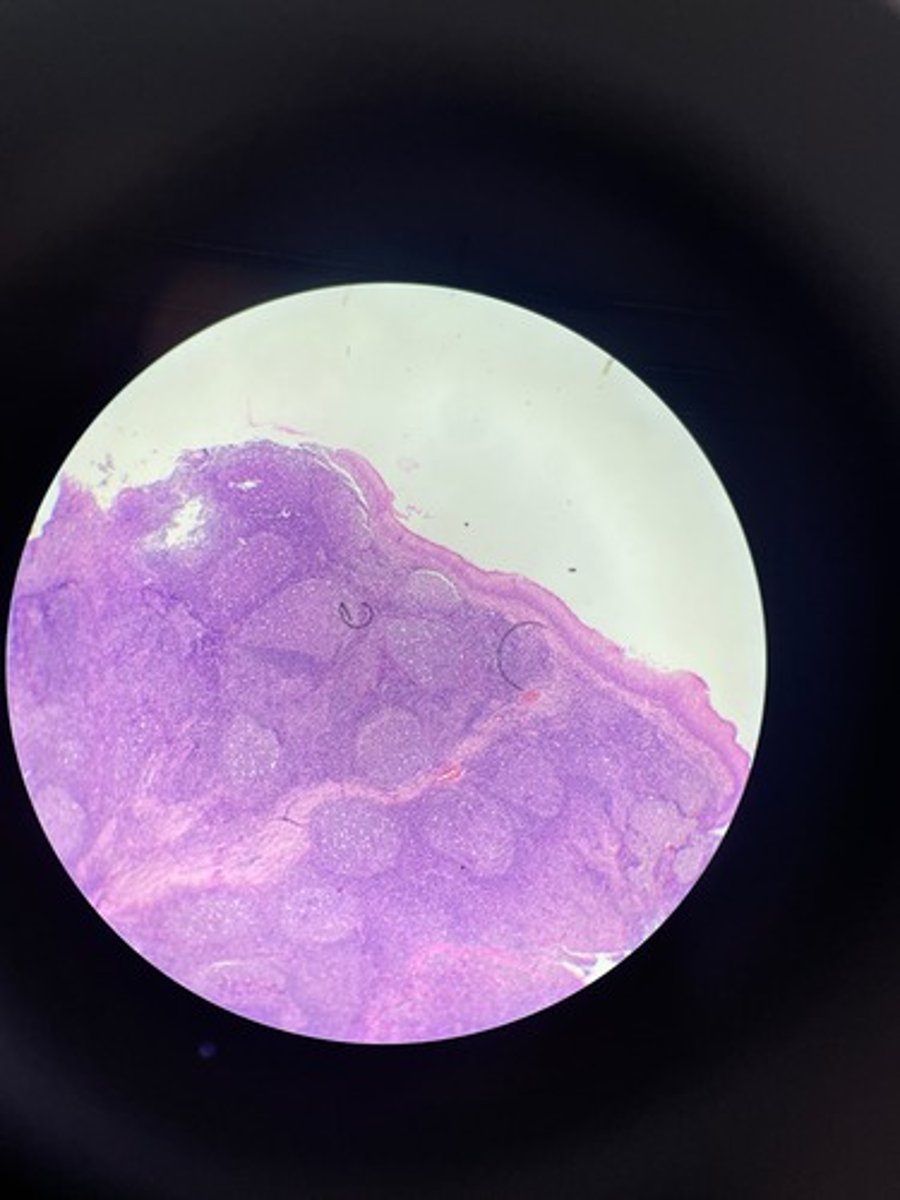

Tonsils HE

Tonsils HE

Tonsils HE